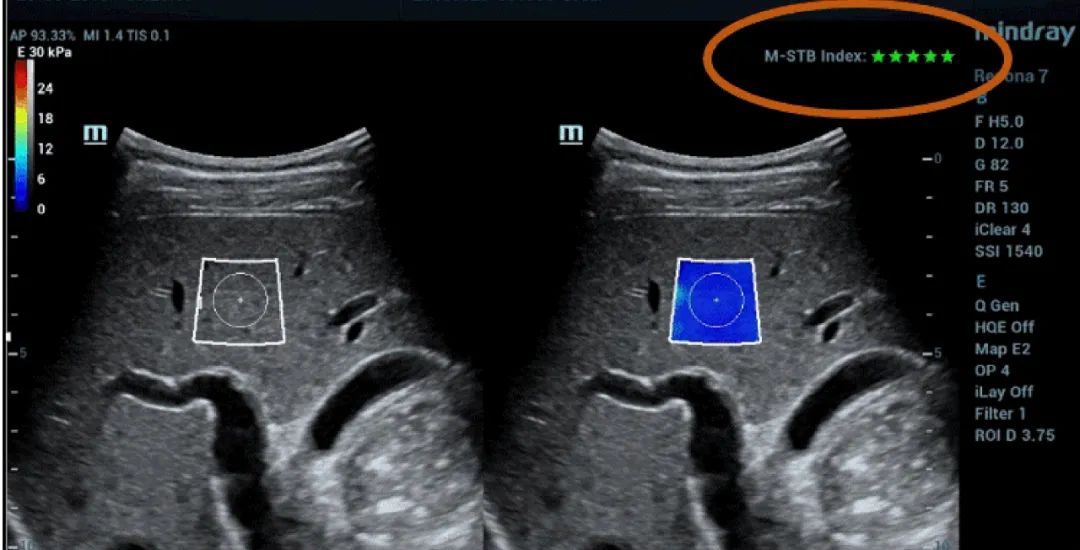

Şekil 1 (devamı): (e) 2D SWE (STE; Mindray, Shenzhen, Çin) ile elde edilen görüntüler. İki kalite kriteri sağlanmıştır: Yıldızlarla gösterilen (en yüksek kararlılık beş yeşil yıldızla gösterilmiştir) hareket kararlılığı (M-STB) endeksi ve mordan yeşile giden (İkincisi en yüksek güvenilirliği gösterir.) güvenilirlik (RLB) haritası. Yıldızlar, edinim sırasında hareketin bir göstergesidir. Dört yıldızdan az olduğunda, edinim sırasında önemli hareket vardır ve bu çerçeve karaciğer sertliği ölçümü için kullanılmamalıdır. (f) Elde edilen görüntüler

M-STB indeksi, hareket girişimini ortadan kaldırmaya yardımcı olan hastanın nefesi veya operatörün kompresyonunun neden olduğu doku hareketinin stabilitesini gösterir. Yıldızlarla gösterilir (en yüksek kararlılık beş yeşil yıldızla gösterilir). Güvenilir bir görüntünün ≧4 yeşil yıldıza sahip olması gerekir.